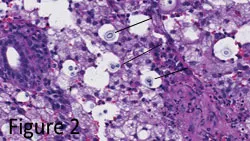

• Narrow-based budding yeast capsules evident (See Figure 2).